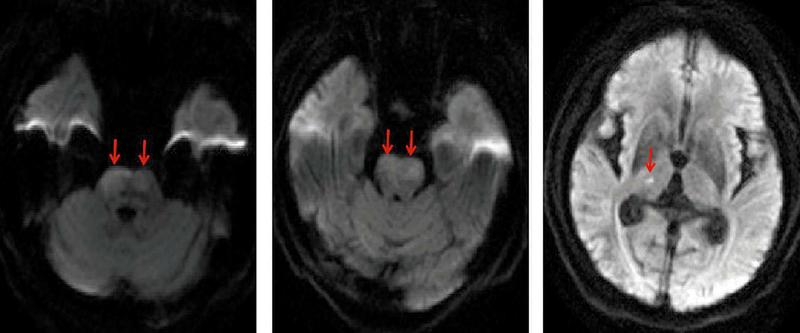

图1头颅磁共振,明确诊断急性后循环多发脑梗死,脑桥双侧受累

本报讯患者洪某,男,68岁,既往长期高血压病史,控制不佳。9小时前晨起时出现头晕伴行走不稳,未重视。5小时前突发意识不清,四肢不能活动,大小便失禁。接诊患者后急诊科、神经内科、影像科及检验科等立即启动脑卒中绿色通道,第一时间完成头颅磁共振,明确诊断急性后循环多发脑梗死,脑桥双侧受累。